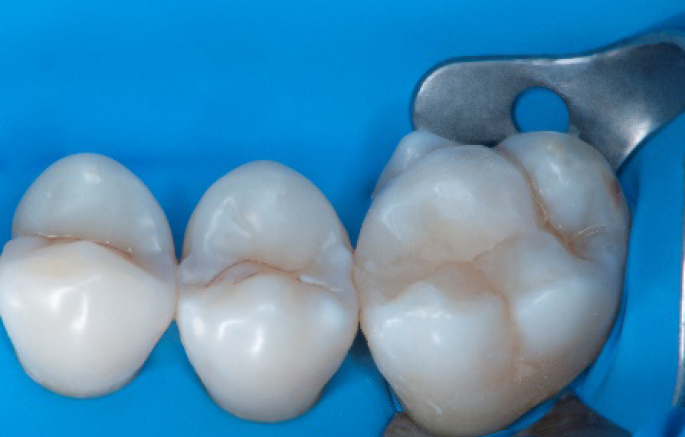

After

Final situation 2 weeks after the filling. Great comfort and no sensitivity at all were reported by the patient.

Step 12:

The situation after rubber dam removal.

Step 13:

Occlusal check

Step 14:

2 weeks control